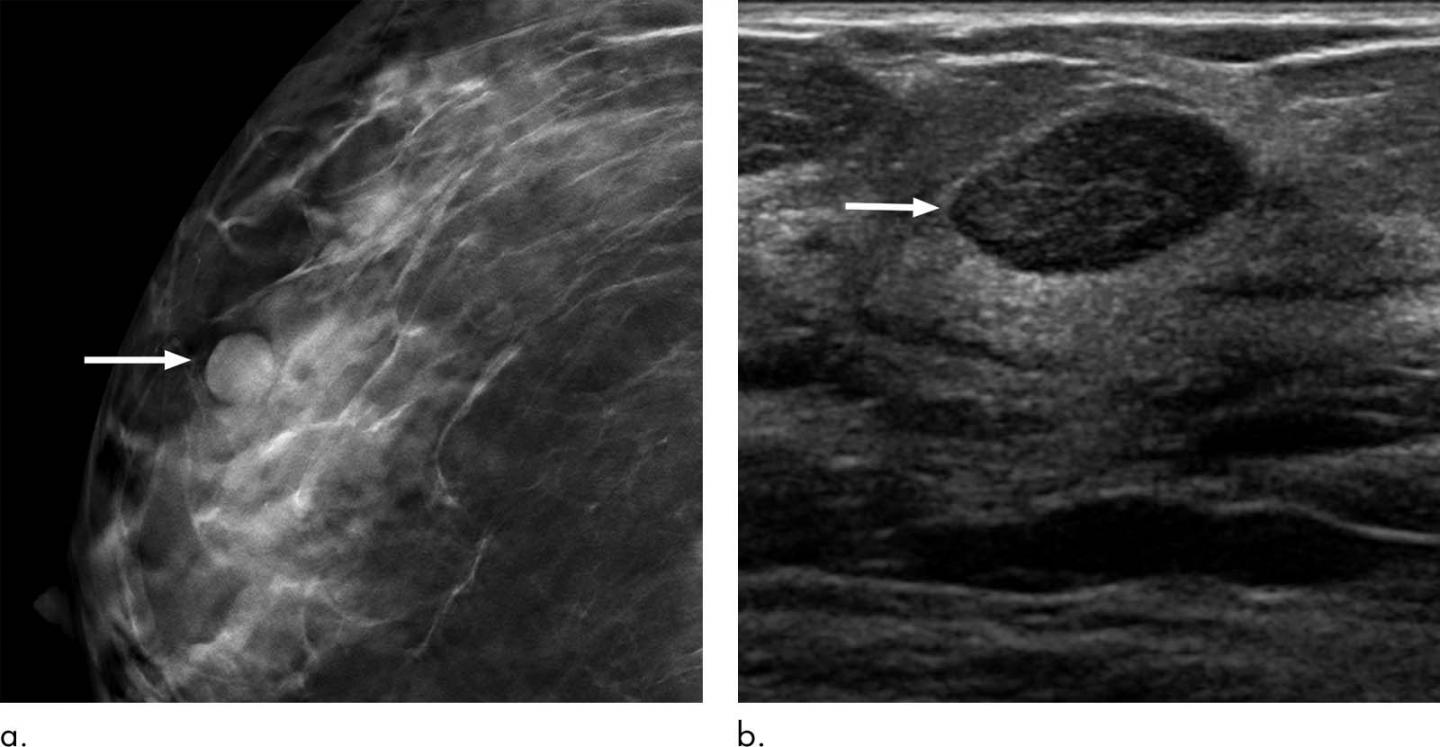

image: Circumscribed mass at baseline screening mammography in a 40-year-old woman due to a fibroadenoma. (a) Craniocaudal tomosynthesis image shows a circumscribed mass (arrow), which was also evident on mediolateral oblique image (not shown). (b) Targeted transverse US image shows a circumscribed hypoechoic mass (arrow), a probably benign finding (Breast Imaging Reporting and Data System category 3). The patient preferred biopsy to surveillance, with US-guided core biopsy showing fibroadenoma.